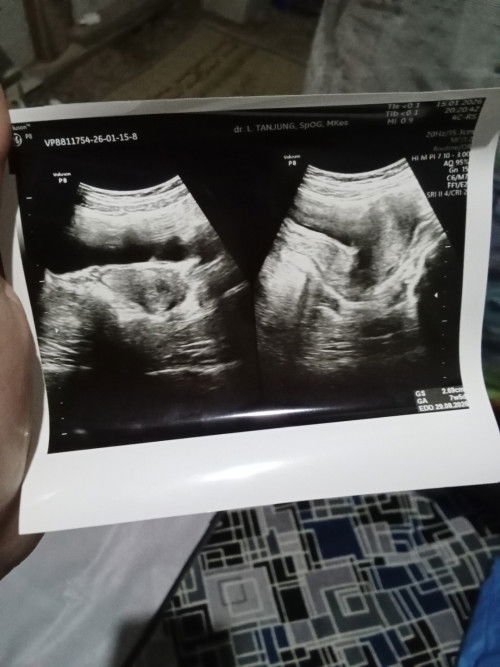

hamil week 10 gejala mual, lemes, males ini itu udh agak hilang. lebih sering laper + sering buang air kecil normal ga bun?, terakhir usg di week 9 itupun baru keliatan kantong kehamilan nya aja blom keliatan janin apalagi djj nya. udh ovt banget takut hamil BO atau janin tidak berkembang:( #mohonbantujawabbunda #firstmom